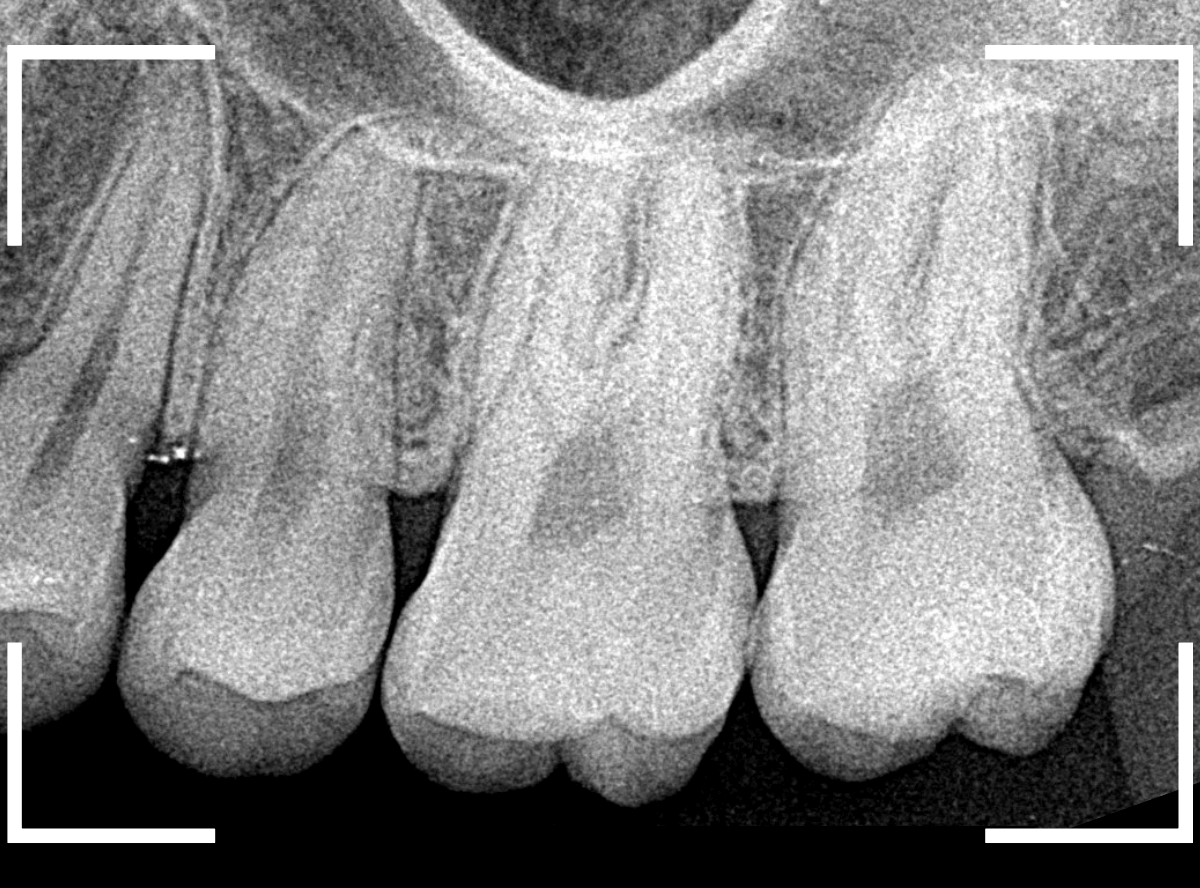

Case.8 大きな虫歯なのに、レントゲンではっきり写らない

こちらも定期検診希望で来院された患者さんです。

お口の中を拝見すると、明らかに虫歯がありました。

3本虫歯になっており、特に中央の小臼歯はかなり大きな虫歯になっているのが予想されます。

治療前にレントゲン写真で虫歯の大きさを確認するつもりが・・・あまりはっきり写ってきません。

患者さんに状況を説明して、歯を少しずつ削りながら虫歯を確認する事になりました。

このように明らかに大きな虫歯があると診断されるような状況でも、レントゲン写真でうまく診断できない場合もあります。